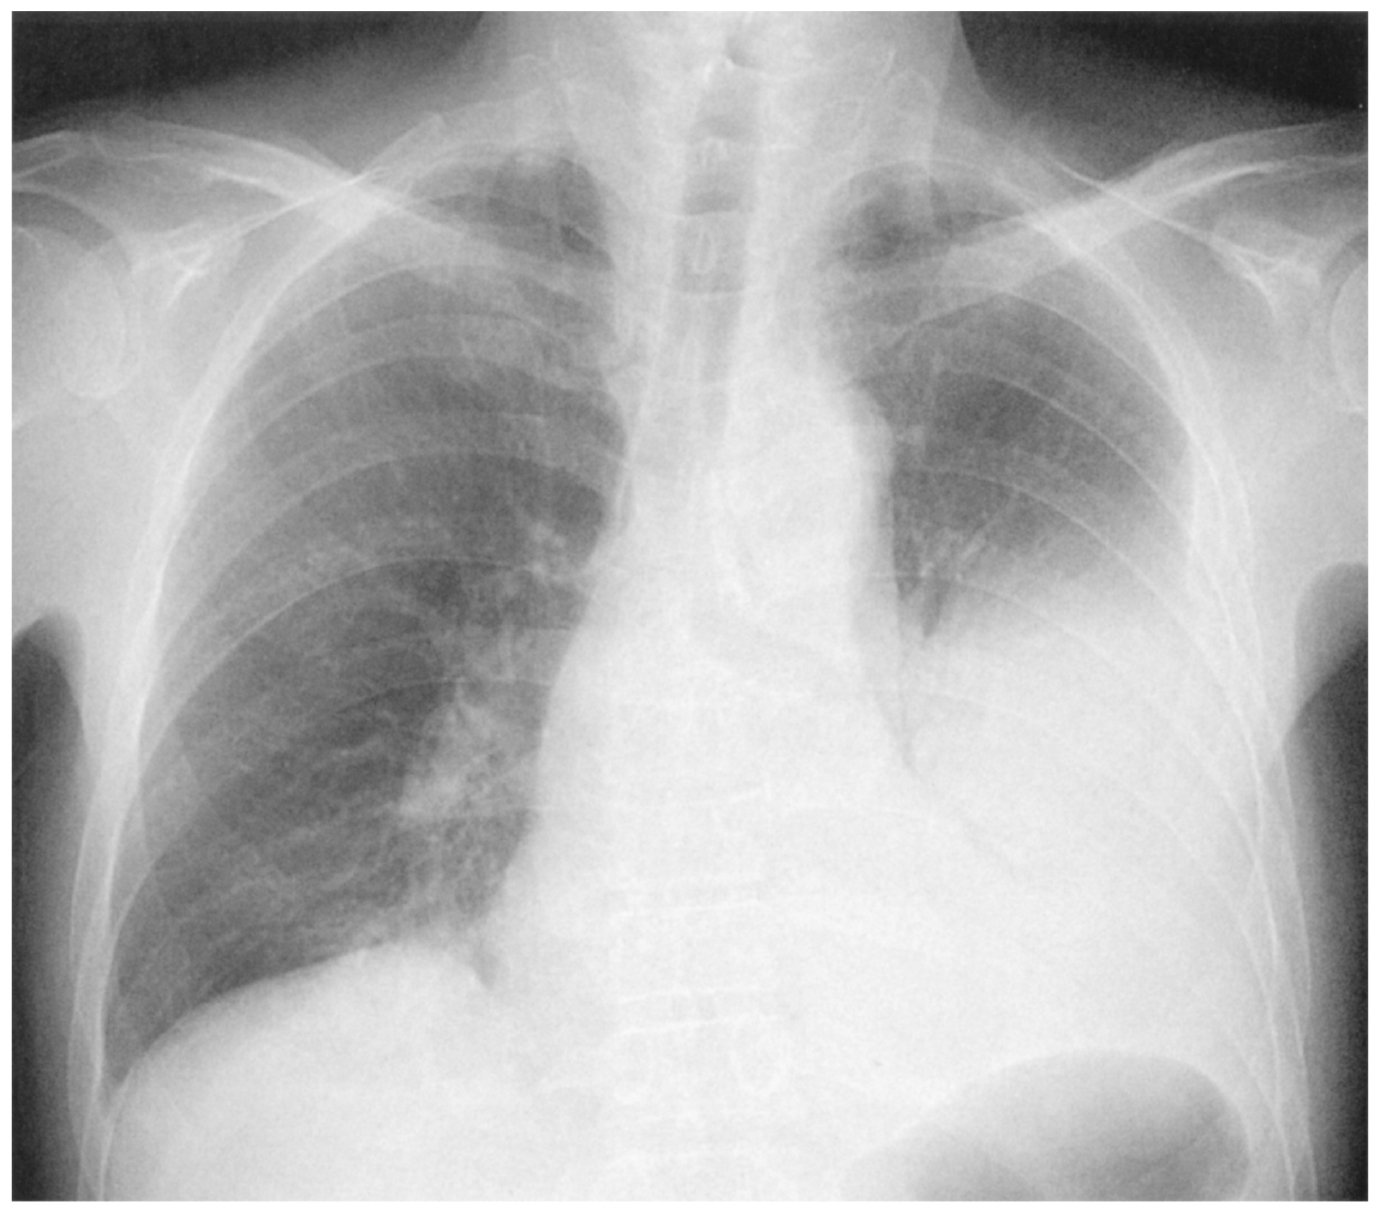

65歳の男性。発熱と胸痛を主訴に来院した。1週間前から咳嗽と喀痰を認めていた。3日前から発熱を伴い,膿性痰が増量し,昨日から胸痛を自覚したため受診した。56歳時から糖尿病の治療中である。60歳の妻と2人暮らし。喫煙は20歳から20本/日を45年間。飲酒は機会飲酒。意識は清明。身長174cm,体重71kg。体温38.3℃。脈拍84/分,整。血圧142/80mmHg。呼吸数20/分。SpO2 96%(room air)。眼瞼結膜と眼球結膜とに異常を認めない。頸静脈の怒張を認めない。心音に異常を認めない。左胸部の呼吸音が減弱している。腹部は平坦,軟で,肝・脾を触知しない。血液所見:赤血球502万,Hb 14.6g/dL,Ht 48%,白血球15,200,血小板23万。血液生化学所見:総蛋白7.0g/dL,アルブミン4.2g/dL,AST 36U/L,ALT 32U/L,LD 338U/L(基準124~222),尿素窒素10mg/dL,クレアチニン0.8mg/dL,空腹時血糖140mg/dL,HbA1c 7.0%(基準4.9~6.0),Na 139mEq/L,K 4.2mEq/L,Cl 103mEq/L。CRP 22mg/dL。胸部エックス線写真を下に示す。左胸腔にドレーンを挿入し,胸水のドレナージを行ったところ,胸水は混濁していた。採取した胸水には白血球を多数認め,Gram染色標本ではGram陽性球菌が確認された。

無料会員登録していただくと、実際の解説をすべて見ることができます。急性の呼吸困難を主訴とする疾患としては,喉頭浮腫,気道異物,自然気胸,気管支喘息,慢性閉塞性肺疾患の急性増悪などの呼吸器疾患,心不全(急性,慢性の急性増悪),肺血栓塞栓症などの循環器疾患が代表的である。この症例では呼吸器感染症と心不全が疑われるが,胸部エックス線写真は肺炎像というよりも両心不全を示唆する所見を示している。診断:心不全(両心不全)(Nohria分類wet and warm) 選択肢考察 ×a 強い呼吸困難,胸痛などにより安静が保てない場合には,血管拡張による前負荷軽減と,交感神経抑制による心筋酸素消費量の減少を目的としてモルヒネを使用する。この症例ではモルヒネが必要となるほどの興奮状態ではない。